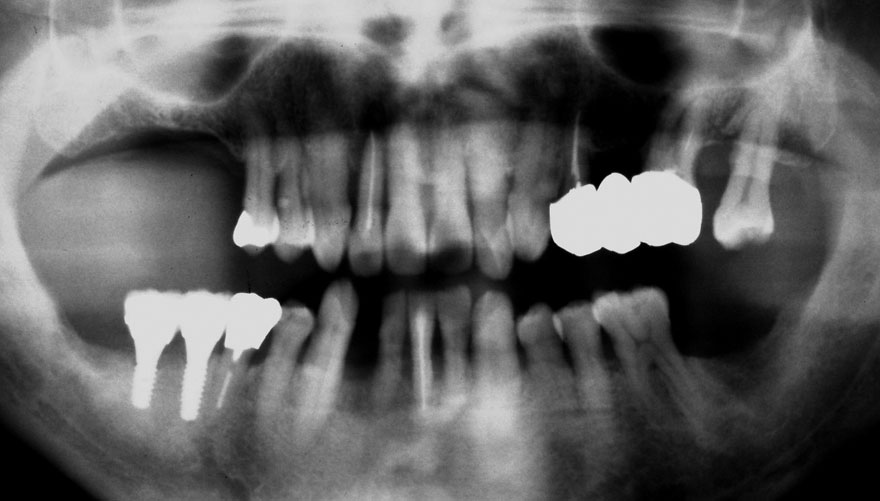

初診時 39歳 女性 平均歯槽骨喪失量:1.82mm

29年後 68歳

平均歯槽骨喪失量:2.21mm

29年間喪失量:-0.39mm

年間喪失速度:-0.013mm

(ケア頻度:5.55ヵ月ごと)